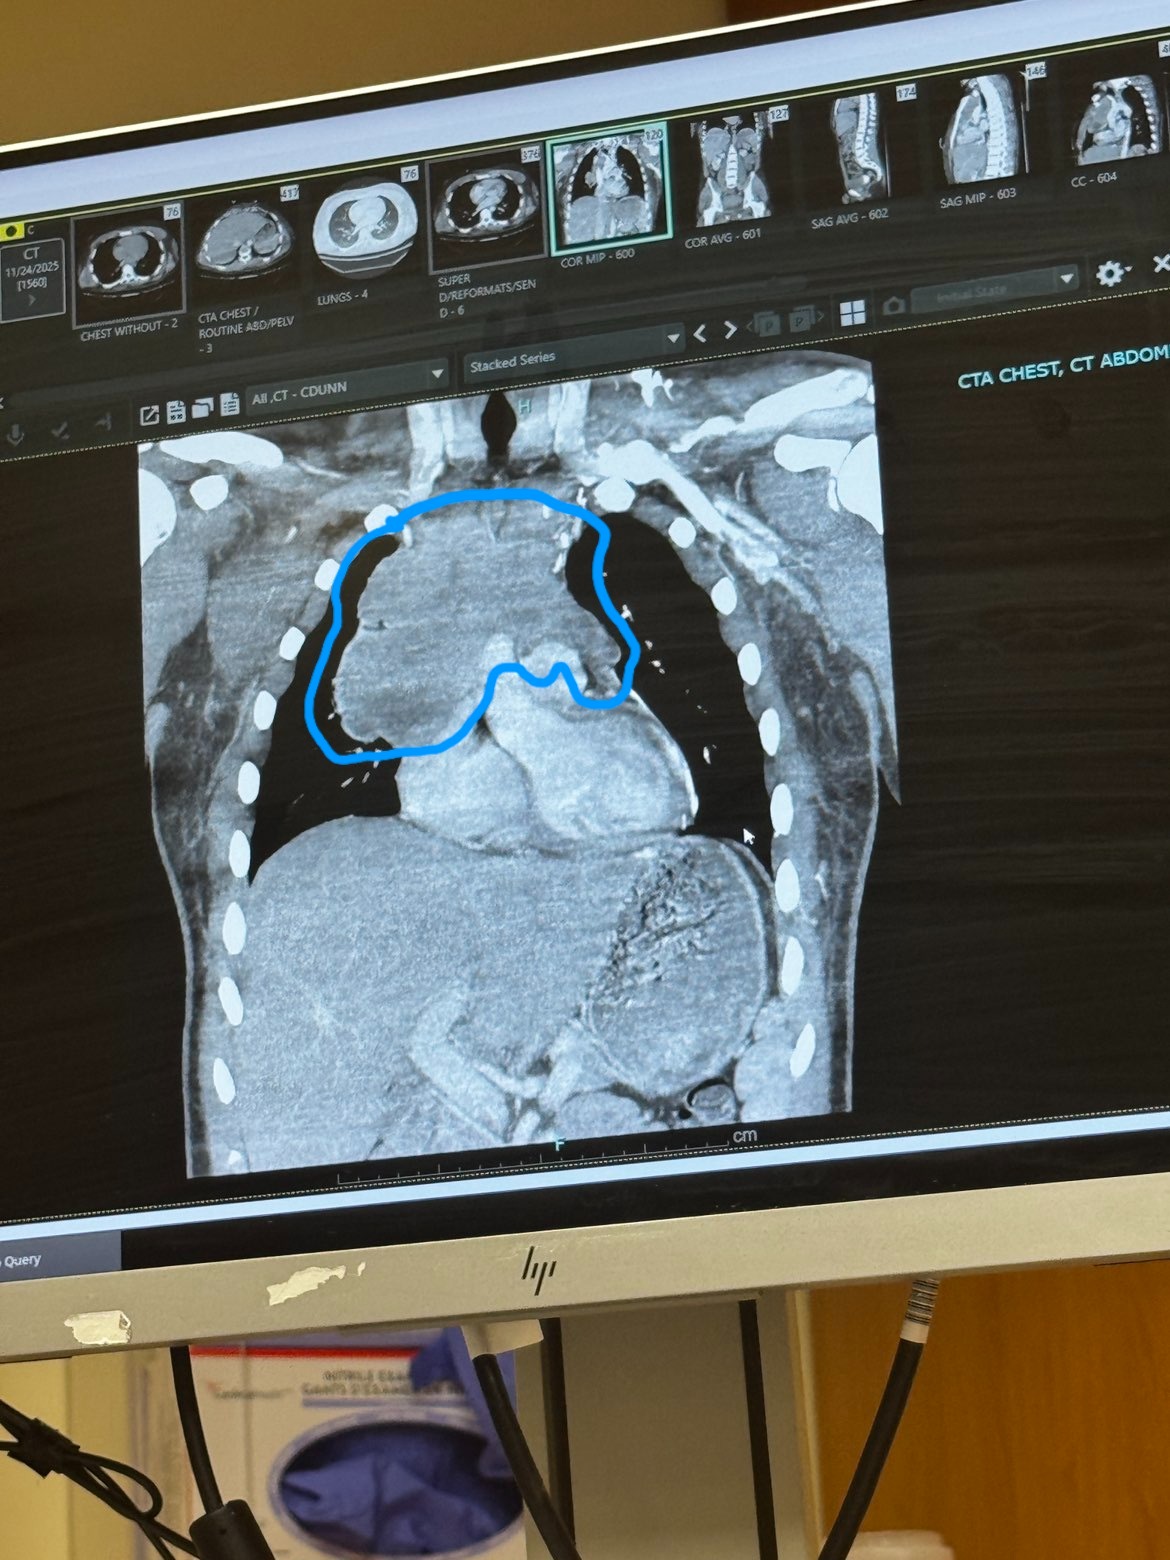

Just days ago, our world changed when Joshua was diagnosed with Non-Hodgkin’s Lymphoma — specifically Diffuse Large B-Cell Lymphoma (DLBCL). What we thought was routine discomfort turned into a devastating discovery: a large mass growing around his heart and lungs, shown in the CT scan image where doctors circled the affected area. This mass has already begun compressing critical structures, making treatment urgent and aggressive.